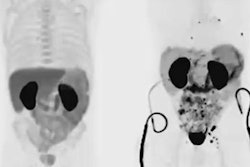

Prostate-specific membrane antigen (PSMA)-PET/CT imaging is comparable to MRI for detecting clinically significant prostate cancer. But MRI is still the more accurate modality for detecting the grade of disease, according to research presented on July 3 at the European Association of Urology (EAU) in Amsterdam, the Netherlands.

Wong's group sought to investigate this theory further via a study that included 240 patients at risk of prostate cancer. Each underwent an MRI exam and a PSMA-PET/CT scan; if imaging indicated that prostate cancer was present, patients had a biopsy.

Although PSMA-PET/CT imaging found more abnormalities than MRI exams did, MRI was more accurate in identifying the grade of prostate cancer than PSMA-PET/CT, at 75% compared with 62%, the team noted. But the two modalities were comparable when it came to identifying clinically significant prostate cancer, Wong noted.